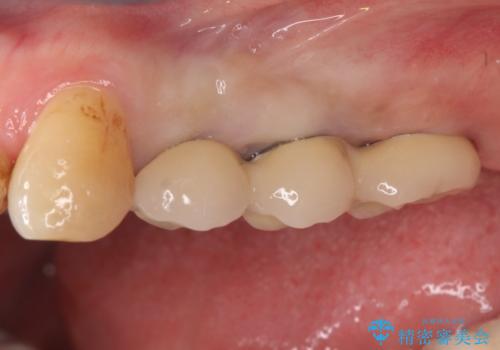

- 奥歯が欠損していることを主訴に来院されました。

インプラントにて補綴治療を行なっております。

綺麗になり、しっかり噛めるようになったと満足していただきました。